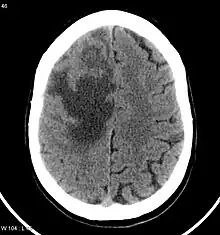

Imaging technology: MRI and CT scans

CNS metastases are diagnosed through imaging techniques that produce detailed images of the inside of the body, including parts such as the bones, organs, muscles, and nerves.[13] Magnetic resonance imaging (MRI) and computed tomography (CT) are two representative imaging procedures for this purpose.[12]

MRI scans use strong magnetic fields and radio waves to create an image, while CT scans use X-rays. MRI scans produce more detailed images of bodily structures, particularly soft tissues including the brain,[13] and are better at detecting CNS metastases than CT scans. However, CT scans are sometimes used for the initial imaging modality due to their lower cost and efficiency in screening for multiple conditions.[14]